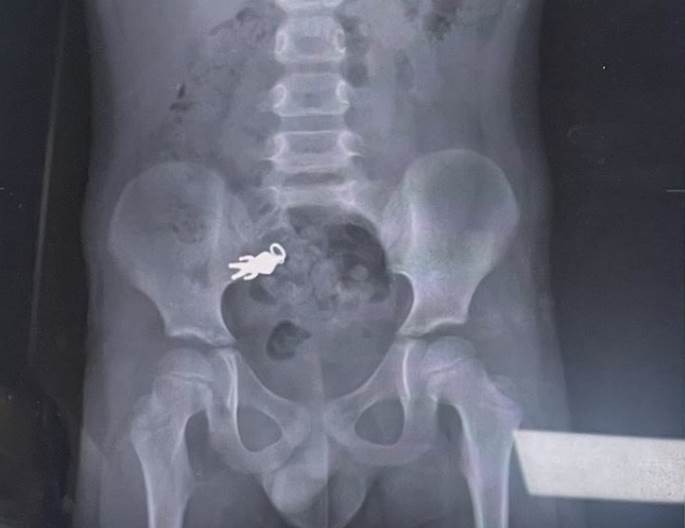

經醫師X光檢查後發現,雖然公仔還在身體裡已進入腸道,但由于看起來並不尖銳、尺寸未超過危險范圍,且男童沒有不適癥狀,醫師建議可等待自然排出,不需手術取出。

羅東博愛醫院小兒科主任謝錦桐分享此個案。他說這起意外發生在上週六,男童因為一心二用,在觀看電視節目的同時享用餅乾,不慎將隨身攜帶的超人力霸王吊墜公仔誤食。家長隨即將孩子送往本院進行檢查,進行X光檢查,影像清晰顯示男童腹部有一個公仔形狀的異物,還能看出上面帶有吊環的特徵。

他說,一般來說,長度超過5公分或寬度超過2公分的異物比較容易在排便過程中卡住,但這個超人力霸王公仔的尺寸約為2.5乘以1.3公分左右,未超過這個范圍,且已順利到達腸子部分,而小朋友目前沒有任何癥狀,因此建議家屬回家繼續觀察一兩天。